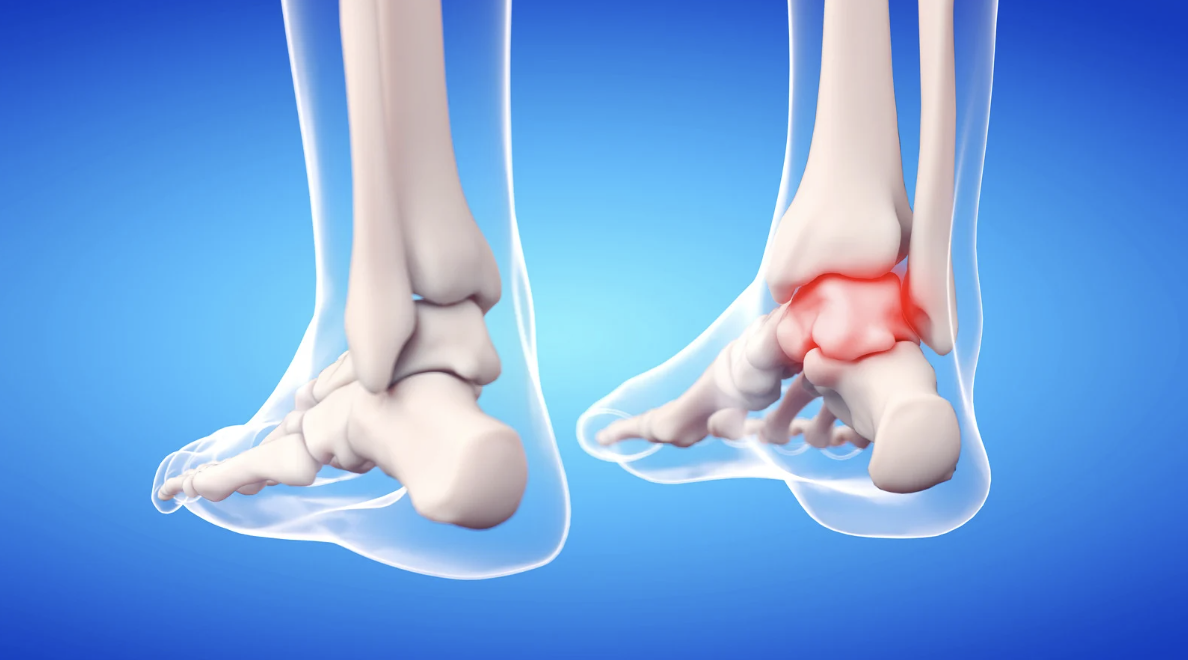

Entre los problemas más comunes en esta etapa se encuentran la fascitis plantar, metatarsalgia, juanetes, dedos en garra, callos y dolor de talón. Estos pueden manifestarse como:

- Inflamación o enrojecimiento.